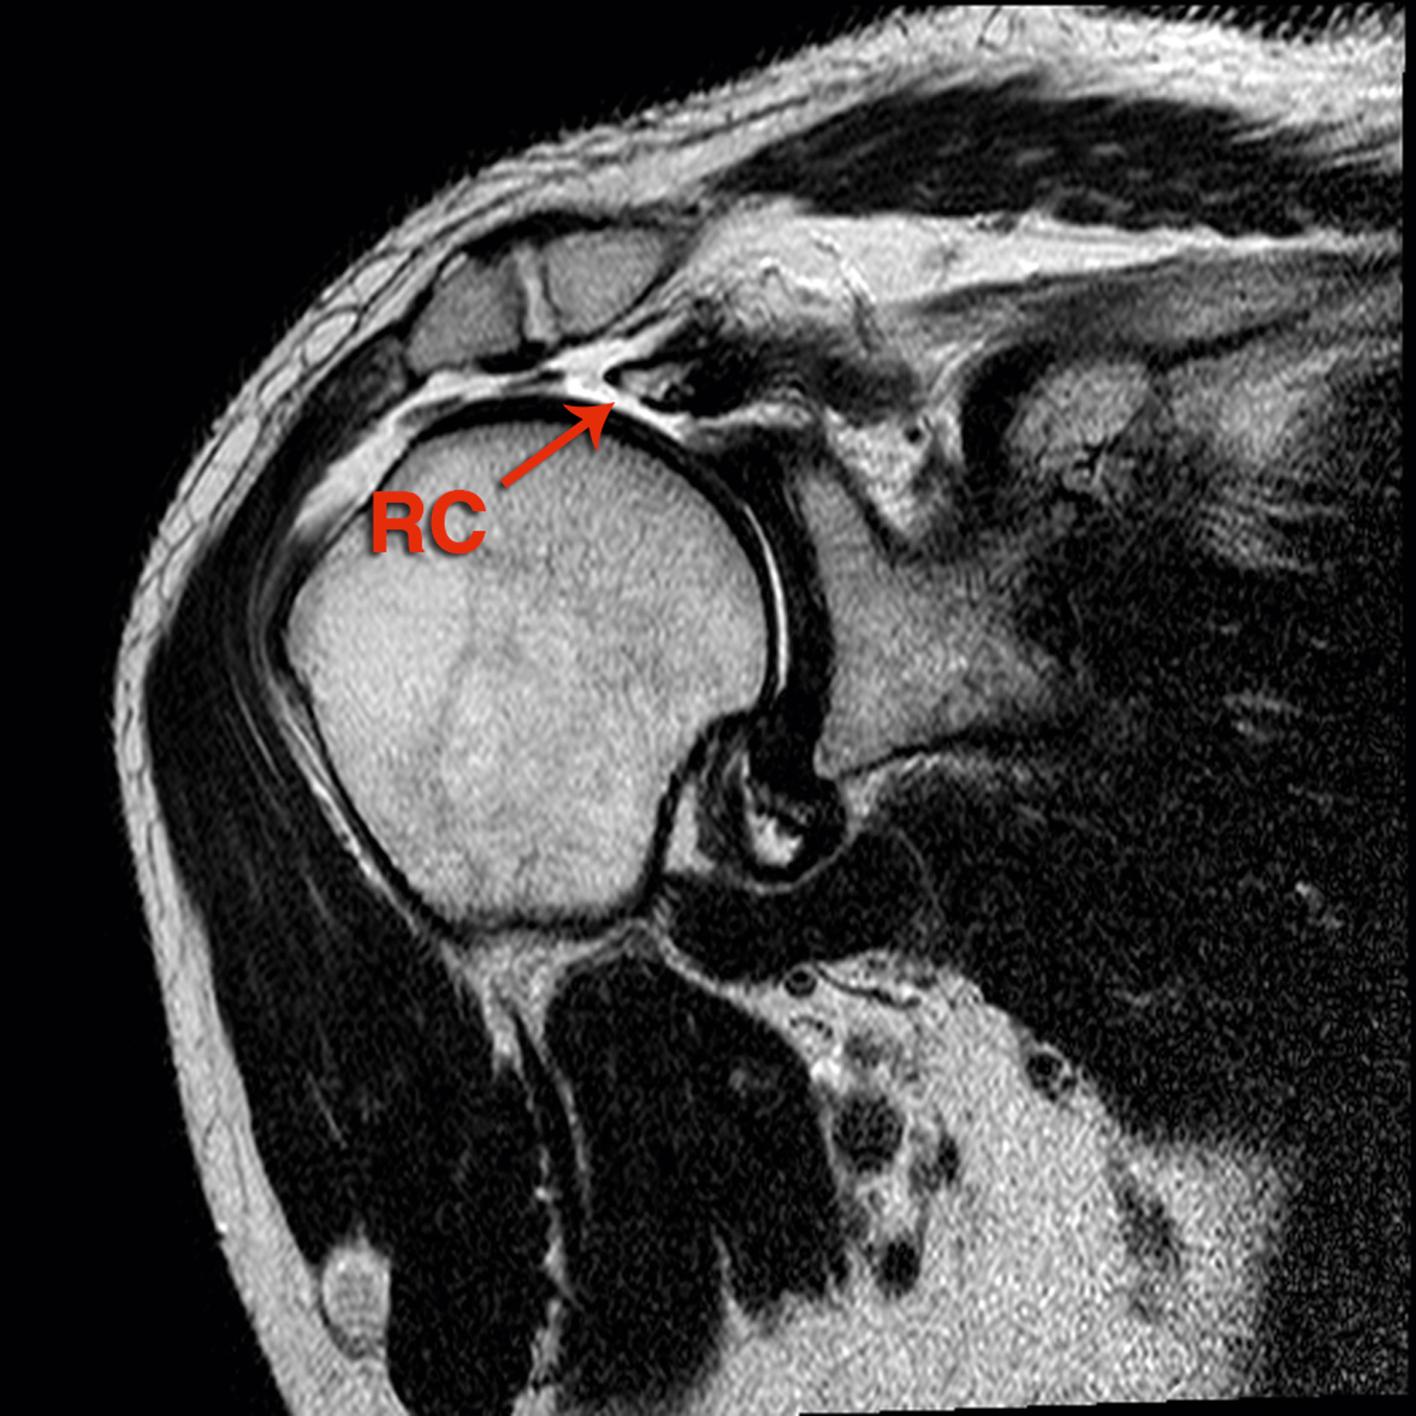

FIG. 7.1, MRI coronal view of the right shoulder with irreparable cuff tear planned to undergo superior capsule reconstruction. RC , rotators cuff remnant.